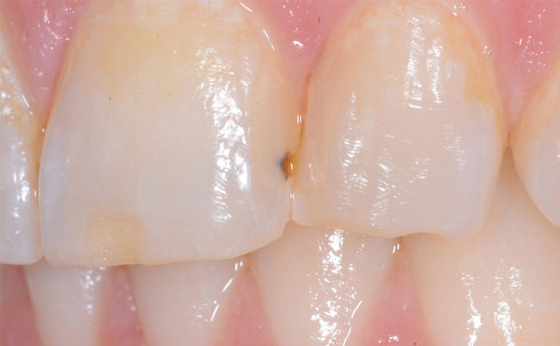

2. Durch Blasen verursachte Flecken auf der Restauration

Wenn eine Blase eine Vertiefung auf der Oberfläche eines Komposits hinterlässt, können Schönheitsfehler mit peinlichen Verfärbungen entstehen.

Eine kleine Blase im Komposit weist eine erhebliche Verfärbung auf, über die sich der Patient beschwert hat und die der Grund dafür war, dass er den Zahnarzt gewechselt hat.